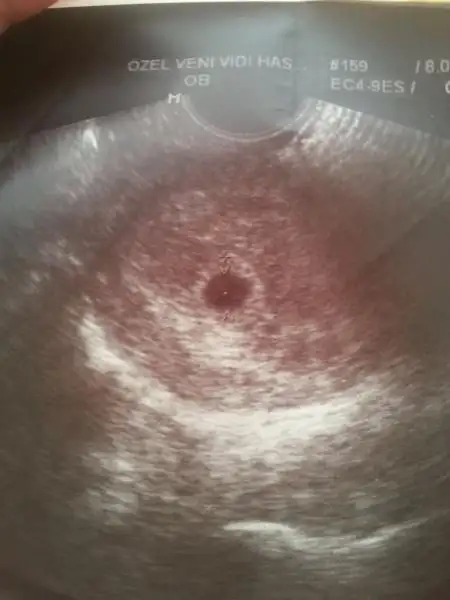

yok canım minicik deil fotoya bakıyorumda kese olan yer siyah ve 1 pirinç tanesi kadar:9: onun içinde minicik beyaz nokta var oda bebişş:34: canım foto verdimi sana doktor bak benimki bu Eki Görüntüle 1210707

canım fotom var da benimki minik bir nokta sanırım benimki daha küçük oldugu için daha 2,6 mm benimki doktor 2-3 haftalık demişti:55::55::55:masallah canım benimkide haftaya belli olur iyce insallah canım Allah korusun onları:nazar::nazar::nazar:

ayy kıyamam cidden minnacıkmış senin ya:38: benmki 6mm e hadi inş iyicene tutunurlar:emir_bebek: